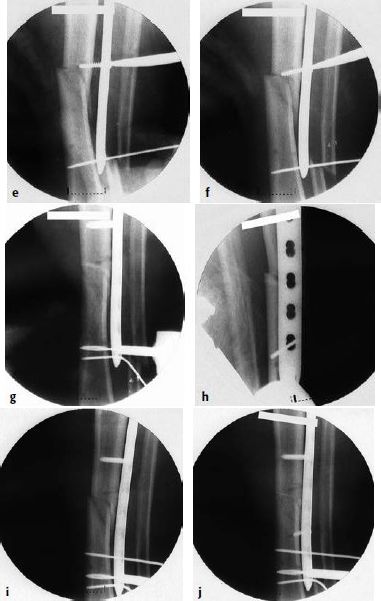

图6.8.1-17 a-n 一名62岁的男性车祸后左腿受伤(41A3.3)

a-b  X线显示左侧胫骨的节段性骨折。骨折近端有多条骨折线和一个楔形骨块,但是它们都没有移位或移位程度很小。整个骨折可以通过一根髓内钉进行固定,但是由于骨折位置非常高位,因此髓内钉手术将非常具有挑战性,因此最终选择采用MIPO技术进行钢板固定

c-d  关节面的骨折通过软骨下螺钉进行稳定固定,使用点式复位钳通过微创技术经皮复位近端的干骺端骨块,滑入胫骨近端锁定加压钢板,而后使用两枚克氏针在钢板两头进行临时固定

图6.8.1-17 a-n(接上图) 一名62岁的男性车祸后左腿受伤(41A3.3)

e-f  通过一枚单皮质复位螺钉将中间节段拉向钢板

g-h  在骨折区的内侧进行手法加压使得干部复位

i-j  当钻透坚硬的皮质时,干部会被推开,而后再次通过一枚单皮质复位螺钉将其复位

k-n  关节面的骨折通过软骨下螺钉进行稳定固定,使用点式复位钳通过微创技术经皮复位近端的干骺端骨块,滑入胫骨近端锁定加压钢板,而后使用两枚克氏针在钢板两头进行临时固定。

术后X线的力线可以接受。注意骨折的每个部分,工作长度都长达3个螺孔(双头箭头)。拉力螺钉打入近端骨折区来维持楔形骨块。但是一般来说,并不推荐在桥接区域放置拉力螺钉,因为它可能会妨碍跨骨折区的微动,从而妨碍骨折愈合。远端内侧的钢板位置稍微偏前以避免和外侧锁定板的螺钉钉道发生冲突。所有的骨折最终均平稳愈合